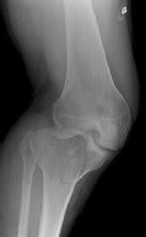

**CLINICAL SITUATION**

Figures 1 and 2 are the radiographs of a 35-year-old man who is brought into the emergency department after a motor vehicle collision. He is complaining of isolated knee pain. Examination reveals swelling, blood filled blisters, popliteal ecchymosis, joint line pain, and limited knee joint motion. His pulses and sensation are normal.

This knee injury is best described as a

Initial surgical management should consist of

Figures 3 through 8 are the axial and sagittal CT scan sections of the injury. Intra-operative patient positioning for definitive fixation should be

The surgical approach for definitive reduction and stabilization of this pattern is